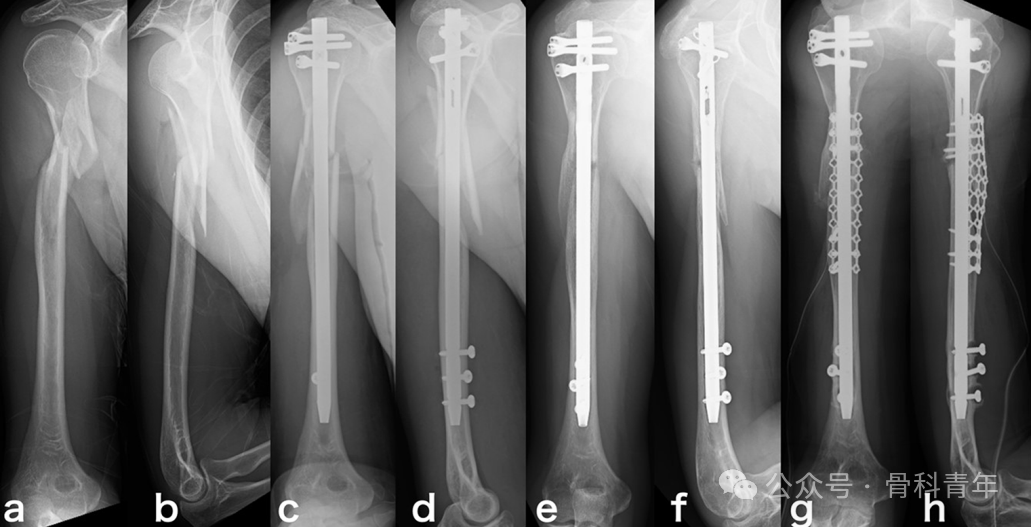

肱骨干“碟形骨块”

肱骨干“蝶形骨块”多见,文献介绍了合并蝶形骨块的肱骨干骨折(a,b),行髓内钉固定后,蝶形骨块未固定(c,d),术后12月出现骨折不愈合(e,f),后经植骨翻修(g,h)。

而一期行钢丝环扎组,则获得了预期的骨愈合。

文章结果表明,对合并蝶形骨块的肱骨干骨折,尽管钢丝环扎或增加手术时间和增加术中出血,但能避免骨不连。提示钢丝环扎有益。